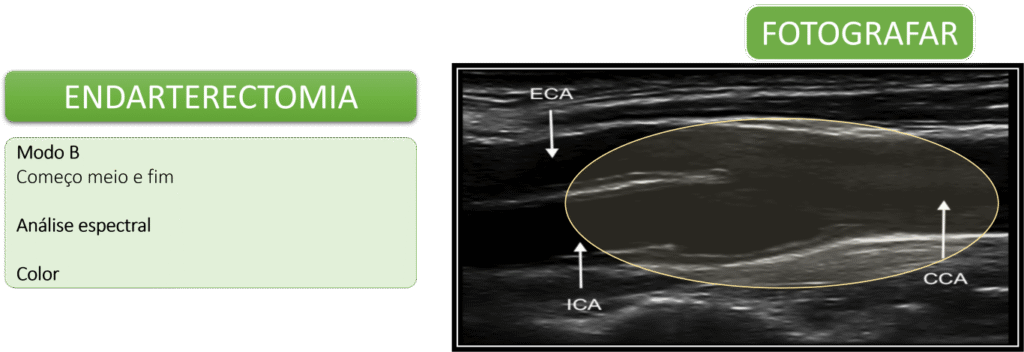

Imagens para registrar

O Doppler de carótidas é uma ferramenta fundamental para avaliar doenças arteriais.

Além da observação dinâmica em tempo real, é essencial registrar imagens que contenham as informações mínimas necessárias para um diagnóstico preciso.

Essas imagens devem incluir cortes longitudinais e transversais das artérias carótidas comuns, internas e externas. É importante destacar áreas de interesse, como placas, estenoses ou tortuosidades (kinks).

Também é indispensável registrar o Doppler colorido espectral com os valores das velocidades sistólicas e diastólicas — especialmente nas regiões com turbulência ou fluxo alterado.

Esses registros fotográficos permitem uma revisão diagnóstica mais segura e servem como base para comparações futuras, garantindo um acompanhamento detalhado e confiável da evolução das condições observadas.